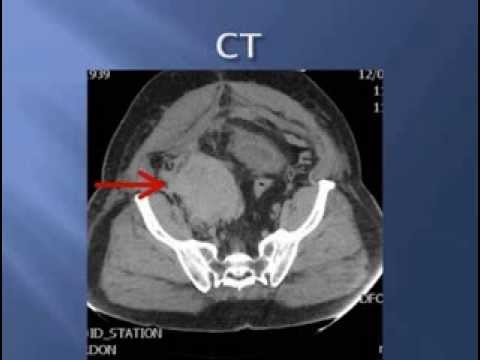

Massive Traumatic Retroperitoneal Hematoma, CT Annotated